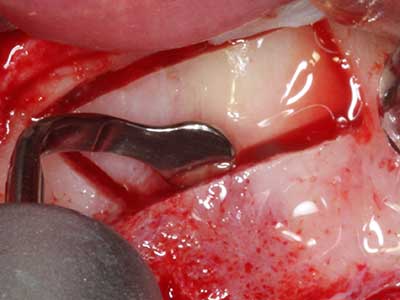

Sollen chirurgische Eingriffe mit unmittelbarer Knochenbeziehung an empfindlichen Strukturen wie Blutgefäßen oder Nerven erfolgen, so bergen rotierende Instrumente ein erhebliches Potential an iatrogener Schädigung. Gerade bei Nervdarstellungen nach iatrogener Schädigung, oder aber im Zuge einer Nervlateralisation für resektive und rekonstruktive Eingriffe oder Implantatinsertionen können piezoelektronische Geräte hilfreich sein Knochendeckel zu präparieren und nervnahe Hartgewebsanteile zu entfernen (Abb. 17-20). Ein leichter Kontakt des Nervstrangs zur Piezospitze bleibt dabei in der Regel folgenlos – allerdings kann eine unvorsichtige Vorgehensweise mit sägeartigen Bewegungen bzw. Ansätzen bei noch vorhandener knöcherner Unterlage durchaus temporäre oder aber auch permanente Nervschädigungen verursachen. Das Risiko einer solchen Schädigung wird jedoch als wesentliche geringer eingeschätzt als unter Anwendung von Säge- oder Fräsinstrumenten (Pereira, Gealh et al. 2014).